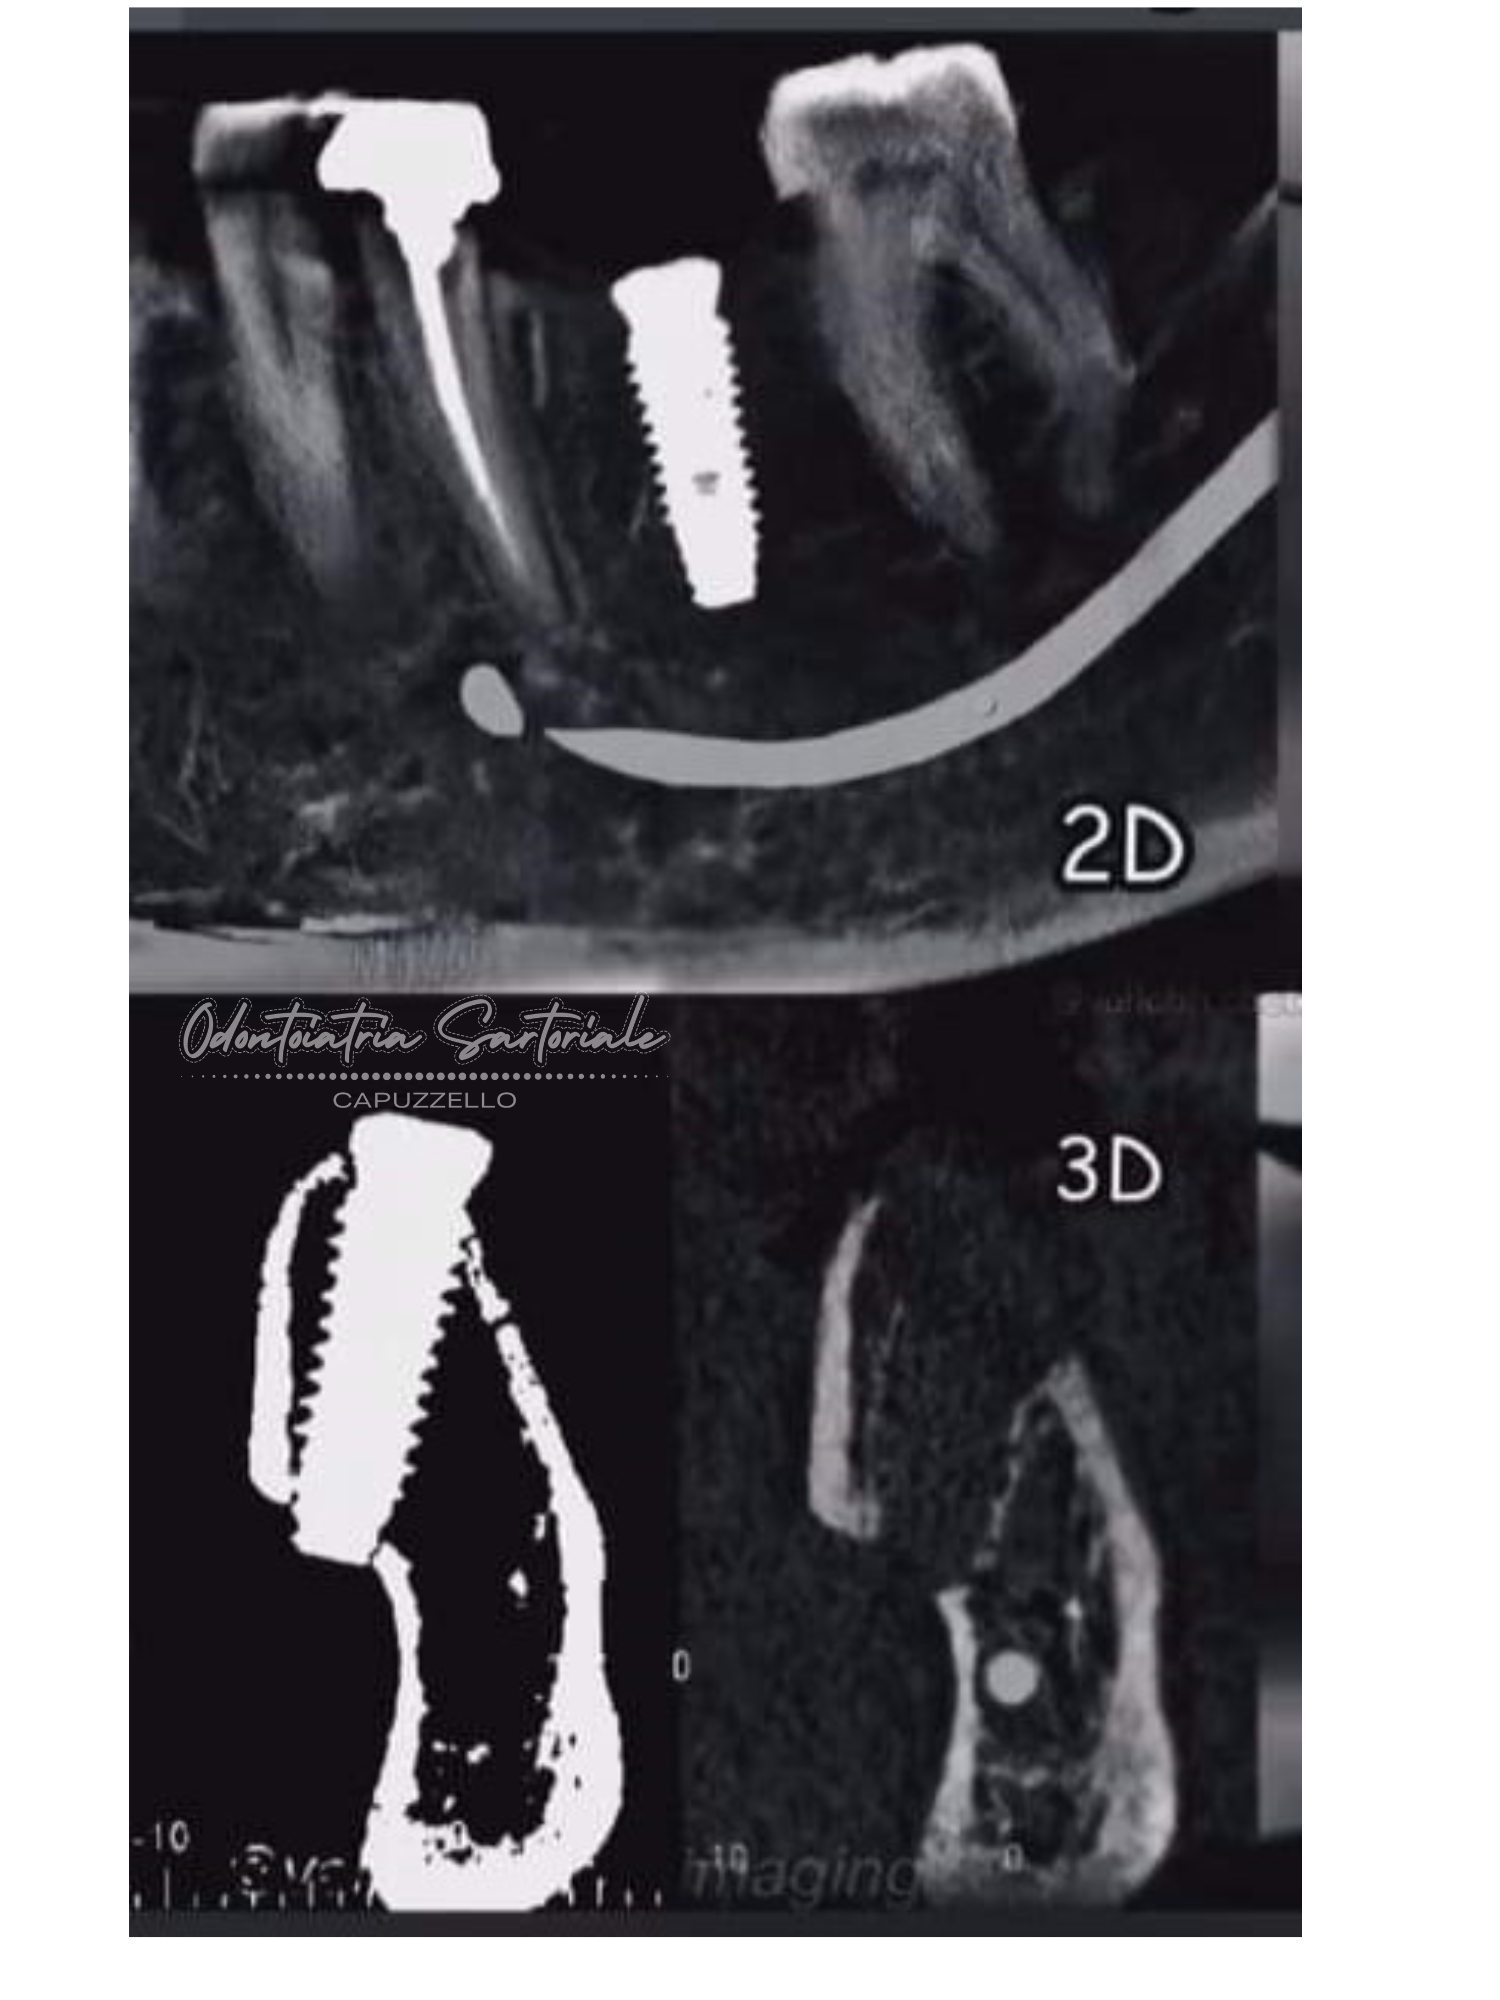

Tac conebeam 3D

Praticare chirurgia implantare utilizzando soltanto diagnostica 2D può avere conseguenze negative.

Questo è il motivo per il quale abbiamo aggiunto da anni l’esecuzione di una tac conebeam 3D alla nostra pratica quotidiana, così che la mano esperta del doc possa programmare ed eseguire in sicurezza i trattamenti implanto-protesici anche in casi al limite.

Ps: la foto nr. 4 non è un nostro lavoro!